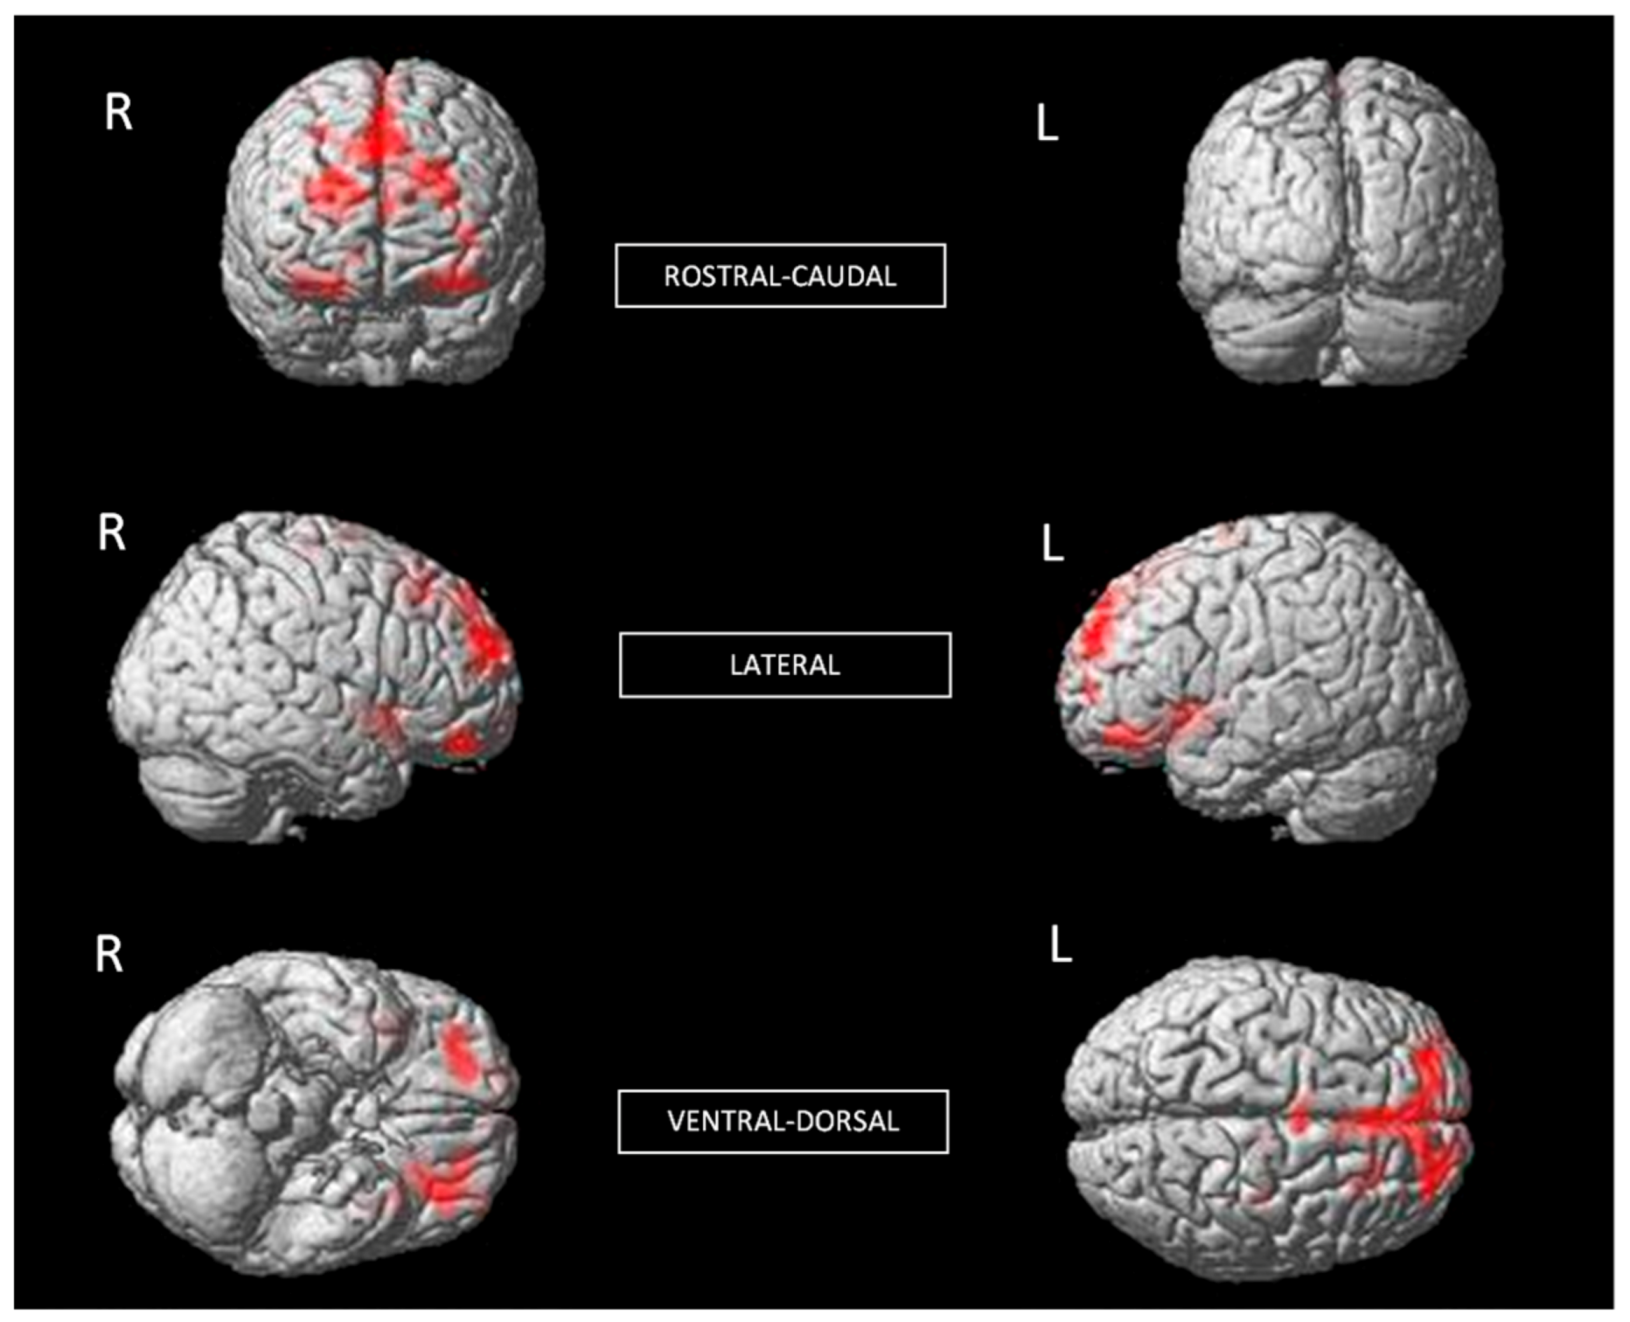

Significant differences between with and without phobia groups appeared in total GMV (group with phobia: mean = 673,26 cm3, SD = 70.85 cm3; group without phobia: mean = 718.81 cm3, SD = 62.49 cm3, F1,60 = 7.20, p = 0.009). Total GMV correlated negatively with SR scores (r = −0.384, p = 0.002). ANCOVA revealed no significant effects of SR or age and did not exceed the cut-off point for considering them statistically significant (F1,60 = 33.56, p < 0.05). The whole-brain voxel-wise analysis showed that, compared with individuals without phobia, individuals with phobia had significantly smaller GMV in the right insula (t (60) = 5.18, p < 0.001); a cluster of right lateral, anterior, and inferior OFC (t (60) = 4.98, p < 0.001); a cluster of left posterior, medial, and lateral OFC, and left insula (t (60) = 4.86, p < 0.001); and a cluster of left superior medial frontal, right superior frontal, and right ACC (t (60) = 4.48, p < 0.001) (Table 1 and Figure 1). In all contrasts, the effect size was moderate.

Additionally, individuals with phobia showed a larger GMV in the left putamen than non-fearful controls (t (60) = 3.48, p < 0.001) (Table 1 and Figure 2), with a moderate effect size. The putamen is related to complex motor regulation and the facilitation of different types of learning.

Figure 1. Significant differences in GMV of brain regions between non-fearful controls (larger) and individuals with phobia (corrected with Gaussian random field theory with a significance threshold of a voxel-wise value of p < 0.001 and cluster probability of p < 0.05).